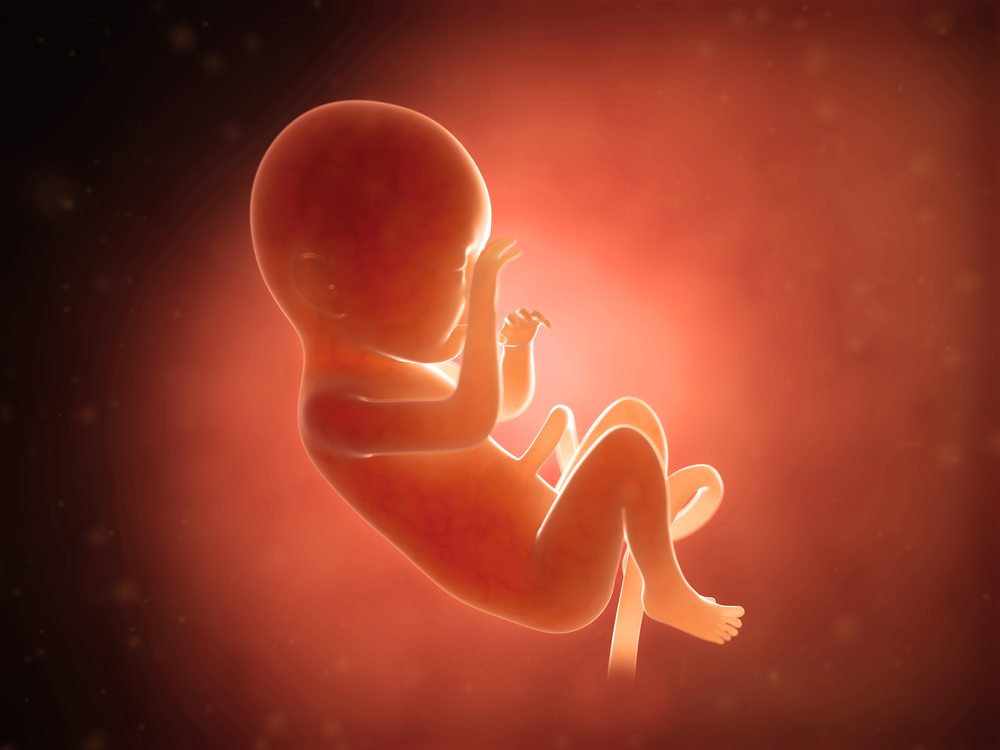

در هفته ششم بارداری، کودک شما تقریباً 1.8 – 1.4 اینچ طول دارد. تقریباً به اندازۀ یک دانه انار. او شبیه به یک بچه قورباغه به نظر می رسد. با یک دم کوچک که به ستون فقرات تبدیل خواهد شد. جوانه های ریزی در راه تبدیل شدن به دست، پا و گوش هستند. مغز، ریه ها و سایر اندام ها نیز در حال رشد هستند. اجزای صورت نیز در همین هفته شروع به شکل گیری می‌کند. دندان ها و یک لایه نازک از پوست وجود دارد. ضربان قلب کودک اغلب با سونوگرافی واژن در این مرحله از بارداری قابل تشخیص است.

در جایی که قلب تشکیل شده است، یک برآمدگی و در جایی که سر قرار دارد، یک حالت تحدب دیده می‌شود. دست و پاهای ریز شروع به شکل گیری می کنند و به عنوان جوانه اندام شناخته می شوند. رویان با لایه نازکی از پوست شفاف، پوشانده شده است. به طور کلی، در این زمان جنین شما هنوز شبیه به یک کودک نیست.